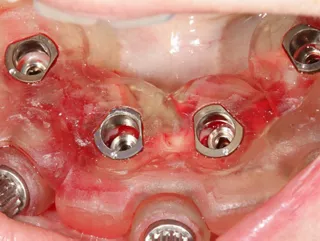

13. Occlusal pictures of healing around the implants at 3 months follow-up upon removal of the provisional prosthesis.

14. Positioning of the transfers in the lower jaw for impression.